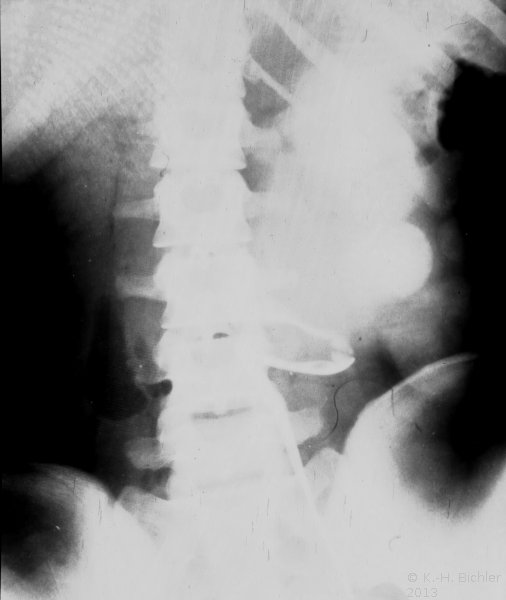

• Abbildung 17: Ureterabgangsstenose mit ausgedehnter Hydronephrose links

4. Resezierter Nierenbeckenanteil und Harnleiterenge

5. Ausscheidungsurogramm nach Ureterabgangsplastik, deutlicher Rückgang des weitgestellten NBKS